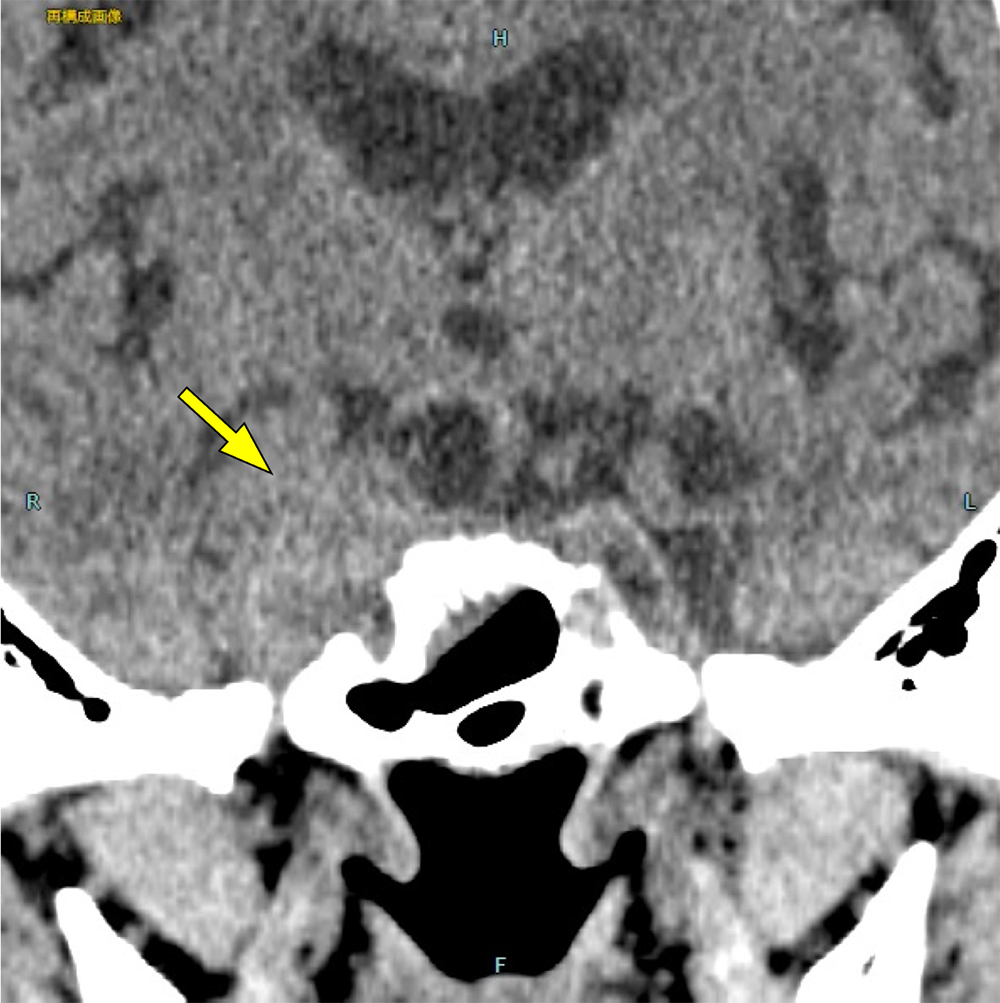

図3.造影CT(早期相)

右内頚動脈が腫瘤に取り囲まれ、対側より狭窄している。